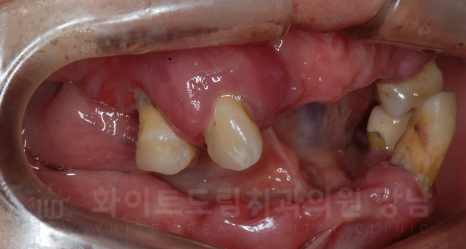

강남역 임플란트 치과, 화이트드림치과 강남 전체 임플란트 사례 (진료 전)

X-RAY 사진을 보면 대부분의 치아가 빠진 상태이고,

그나마 남아있는 치아들도 잇몸뼈에 겨우 매달려 있어 굉장히 심하게 흔들리고 있는 상태였습니다.

심한 치주염으로 인해 대부분의 치아가 빠진 것인데요.

상/하악의 맞닿는 치아가 한 부분밖에 없어 이 부분으로 조금씩 식사하며 지내셨다고 합니다.